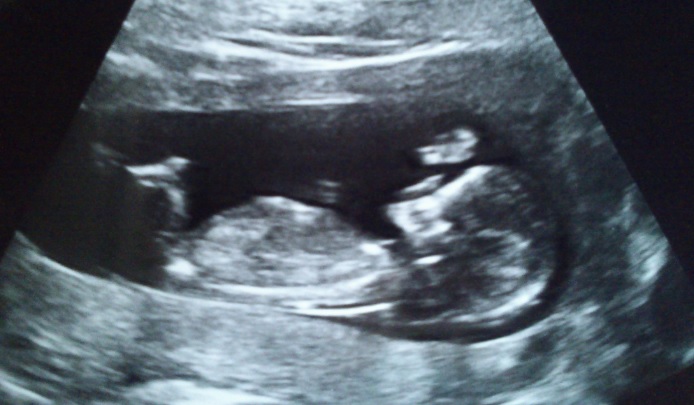

We tried to identify the nub and determine its gender based on the 12w+3d scan but we are not sure.

I think it's the best scan to identify the nub.

We're looking forward to hearing your opinion and thoughts. Is it a boy or a girl?